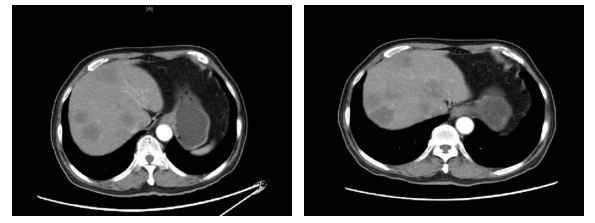

2020.1.5影像学评价:腹部CT:肝脏多发结节,较前增多增大,考虑进展(图3)。

图3. 腹部CT(左:2019.11.18,右:2020.1.5)

2019.11.18 腹部CT:肝脏多发结节(图2),考虑转移。

图2. 腹部CT(2019.11.18)